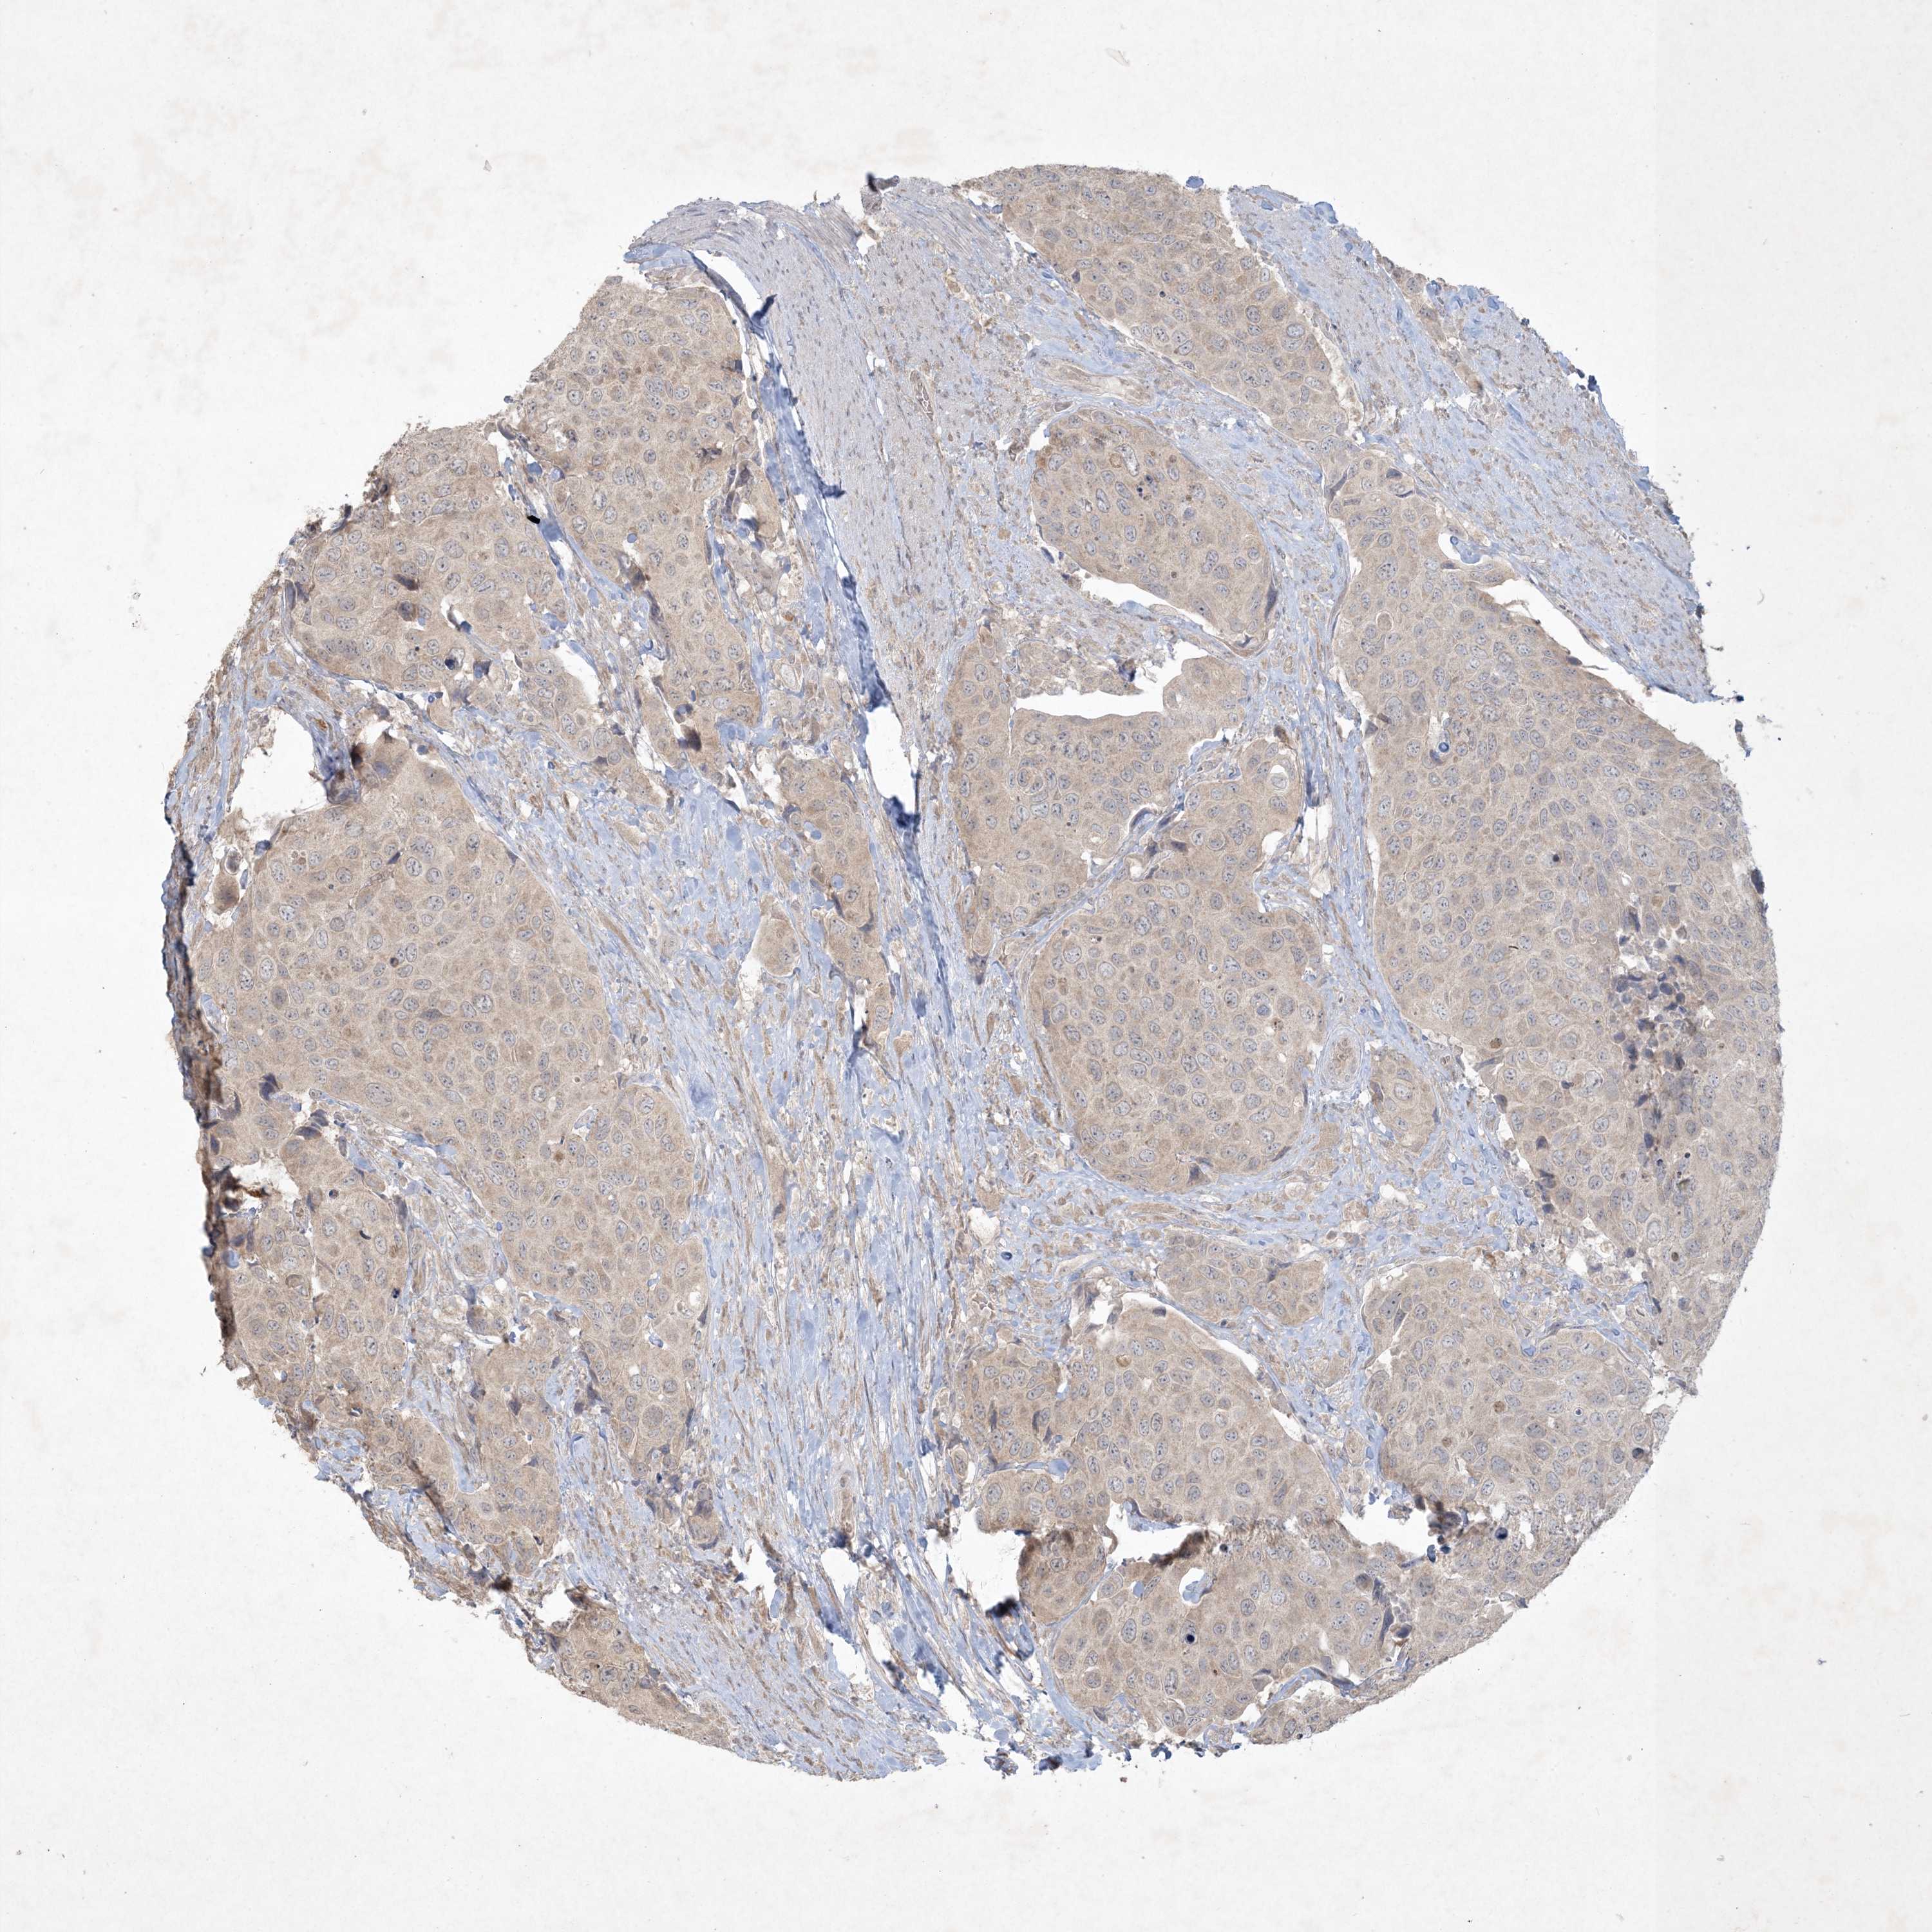

UROTHELIAL CANCER - Protein expressioni

A mouse-over function shows sample information and annotation data. Click on an image to view it in a full screen mode. Samples can be filtered based on level of antibody staining by selecting one or several of the following categories: high, medium, low and not detected. The assay and annotation is described here.

Note that samples used for immunohistochemistry by the Human Protein Atlas do not correspond to samples in the TCGA dataset.

Antibody stainingi

Antibody staining in the annotated cell types in the current human tissue is reported as not detected, low, medium, or high, based on conventional immunohistochemistry profiling in selected tissues. This score is based on the combination of the staining intensity and fraction of stained cells.

Each image is clickable and will lead to virtual microscopy that enables deeper exploration of all samples and also displays staining intensity scores, fraction scores and subcellular localization as well as patient and tissue information for each sample.

Antibody HPA029052

Antibody CAB020944

Urothelial carcinoma, High grade

Urothelial carcinoma, Low grade